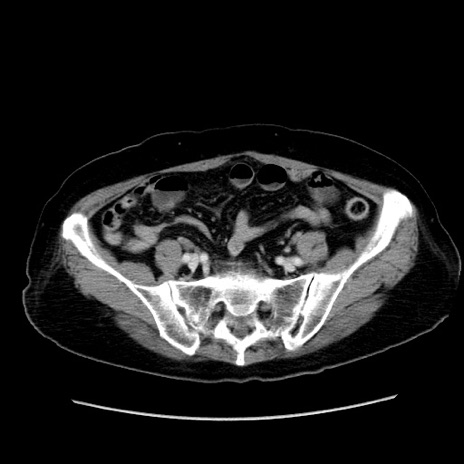

冠状断像

症例19(横断像)

【症例】80歳代女性

【主訴】下腹部痛

【現病歴】約8時間前より下腹部痛の出現あり、救急外来受診。

【既往歴】両側付属器切除

【身体所見】意識清明、下腹部正中に手術痕あり、その部位に一致して圧痛と反跳痛あり。腸蠕動音は亢進。

【データ】WBC 9300、CRP 0.15